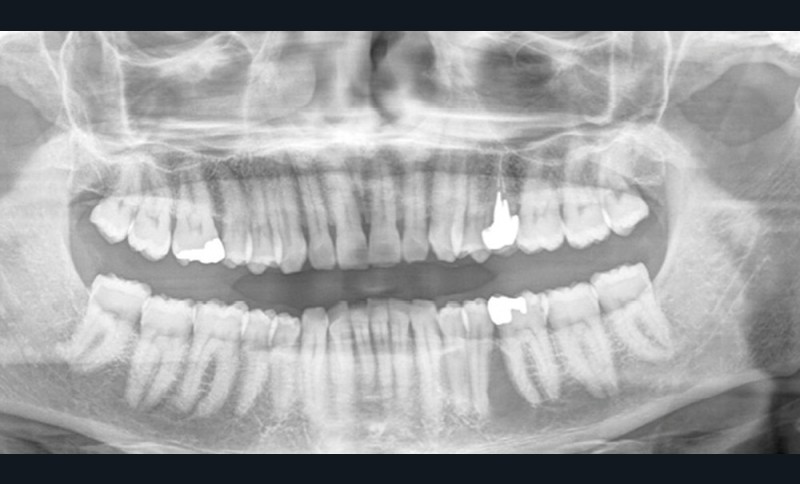

1. Que révèle le Cone Beam ?

a. Des corticales osseuses lysées

b. L’extension de la lésion au niveau du canal dentaire

c. Une rhyzalyse de la 35

d. Des limites lésionnelles mal définies

2. Quel diagnostic évoquez-vous ?

a. Un kyste apico-dentaire

b. Un kératokyste

c. Un sarcome

d. Un carcinome

Réponses 1 : a ; 2 : b ; 3 : d

Commentaire

L’exploration chirurgicale de la lésion a été réalisée sous anesthésie locorégionale permettant de mettre en évidence, après ostectomie, une lésion kystique s’étendant sur les faces linguale et vestibulaire de 35 impliquant l’avulsion de cette dent. L’énucléation de la lésion, à distance du pédicule vasculo-nerveux alvéolaire inférieur, a été réalisée.

L’examen anatomopathologique a conclu à un kératokyste.

Le risque de récidive étant important, le patient a été prévenu de la nécessité de pratiquer un contrôle radiographique annuel par orthopantogramme (OPT), éventuellement complété par tomodensitométrie (TDM) ou tomographie volumétrique (cone beam CBCT).

L’ossification de la perte de substance osseuse est obtenue en 6 semaines mais ne sera visible sur les clichés radiographiques de contrôle que dans un délai de 6 à 9 mois.

Les kératokystes peuvent survenir à tout âge. Ils se manifestent par une voussure osseuse vestibulaire qui peut être douloureuse.

Radiologiquement, la lésion apparaît comme une clarté uni- ou multiloculaire bien limitée. Le diagnostic différentiel peut être posé avec l’améloblastome ; c’est la chirurgie qui permettra le traitement et la conclusion anatomopathologique.